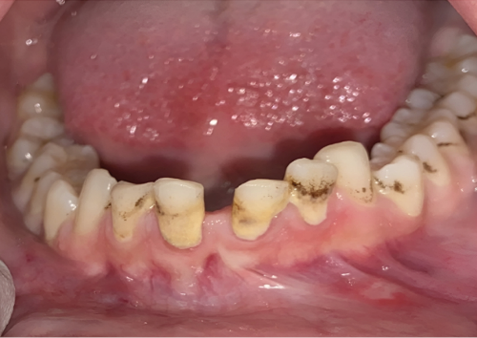

An 18-year-old female student was referred to the Department of Oral and Maxillofacial Surgery at Ain Shams University with a firm to hard swelling related to the mandibular symphysis and parasymphysis region bilaterally, involving all mandibular anterior teeth. The lesion first appeared four months ago as a painful swelling related to the symphyseal region. The patient was prescribed antibiotics and analgesics at the time and the pain eventually subsided. A month later, the patient reported loosening of the mandibular incisor teeth. History of trauma at a young age, pain and increase in facial volume were also reported. Upon clinical examination, the lesion was hard on palpation with crepitus sounds, covered by healthy gingiva and exhibited slight tenderness (Figure 1). Associated teeth 31, 32, and 41 were flared with grade II mobility. Family history, medical and systemic conditions were unremarkable.

Figure 1. Intra-oral examination at the site of swelling extending from tooth 35 across the midline to tooth 43 revealing healthy gingiva and mucosa, flaring in 31 and 41.